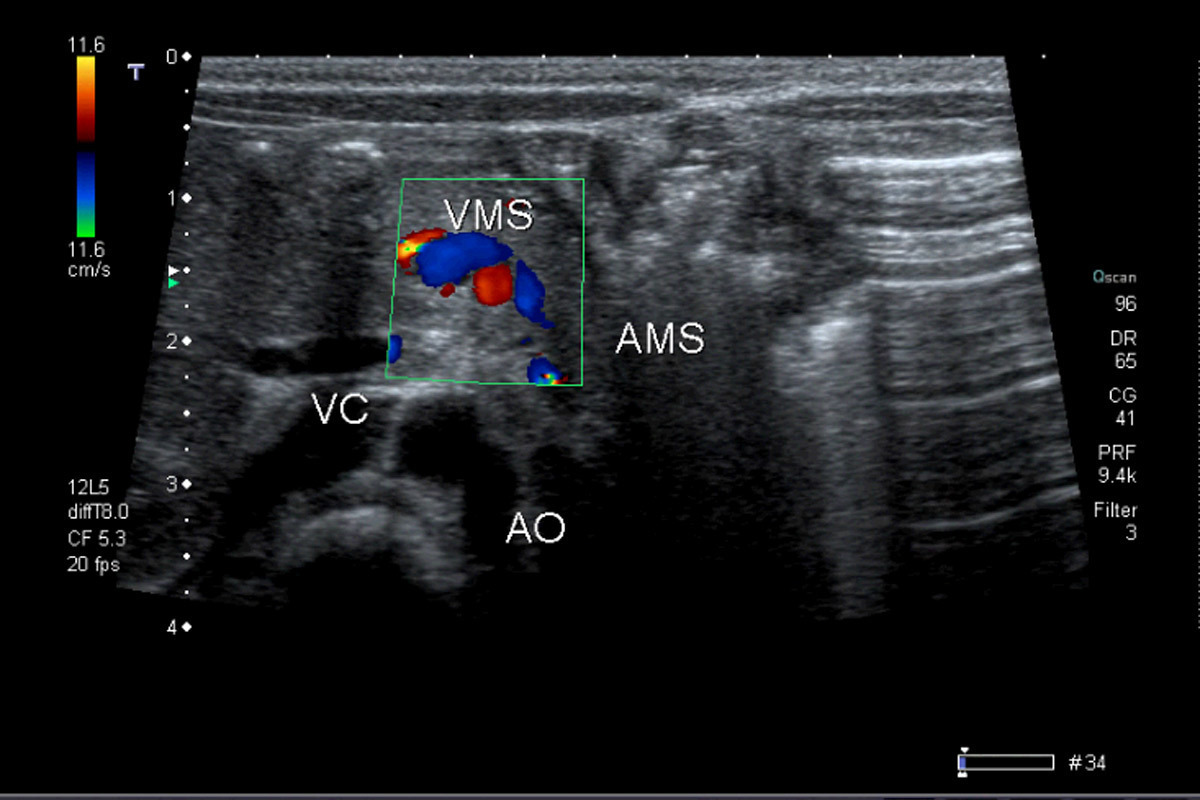

– anatomopathologie/embryologie : accident vasculaire mésentérique pendant la vie fœtale ;